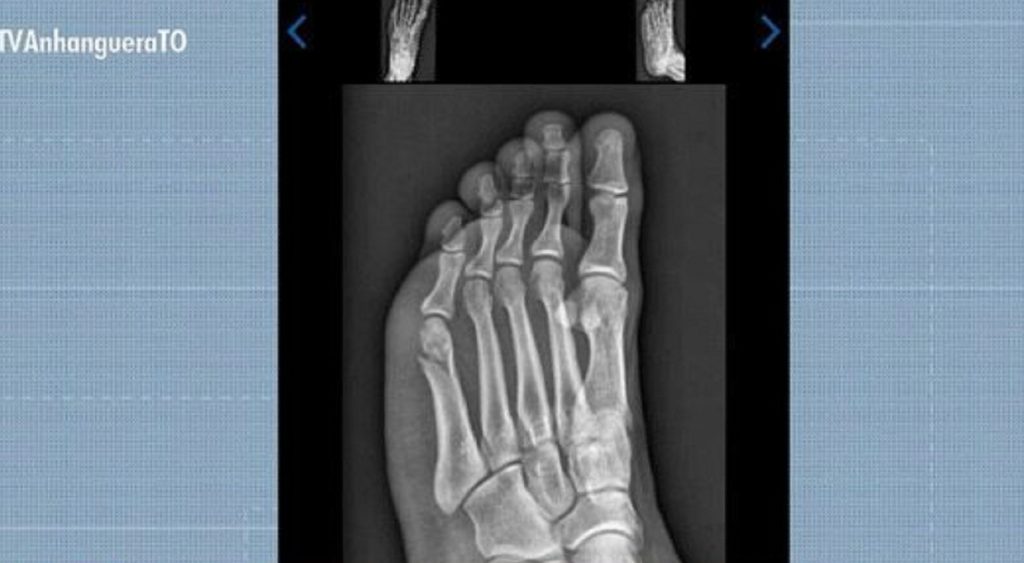

Candidato quebra pé dias antes do TAF da Polícia Militar

Um jovem concurseiro de Gurupi, no sul do Tocantins, conseguiu ser aprovado no Teste de Aptidão Física (TAF) da Polícia Militar mesmo com o pé quebrado. A prova aconteceu 30 dias após Gabriel Santos Rodrigues, de 22 anos, cair do telhado da própria casa enquanto trocava a boia da caixa d’água.

Gabriel Santos Rodrigues foi aprovado no TAF da PMTO mesmo com fratura no pé

Reprodução/TV Anhanguera

Concurseiro concluiu prova de corrida do TAF com fratura no pé